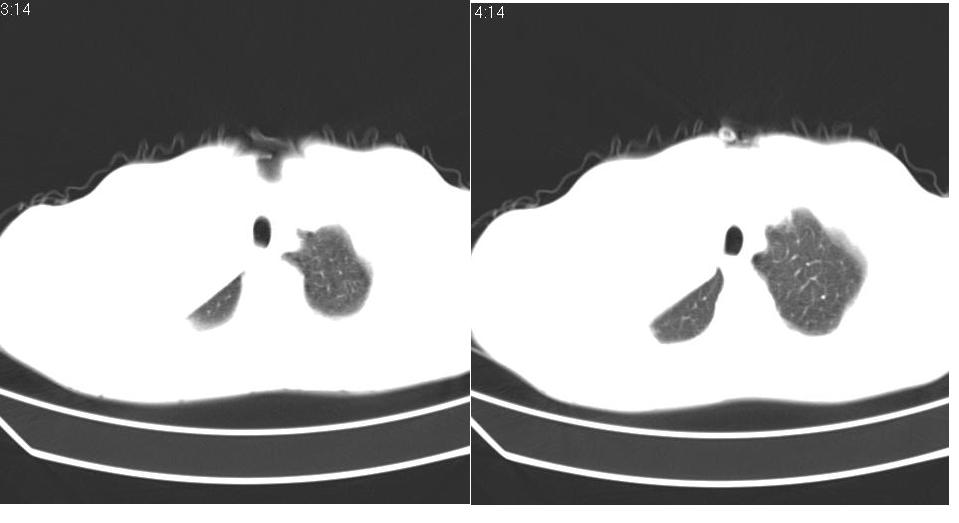

男 58岁 咳嗽,无明显不适.

中央型肺癌伴有右肺上叶不张。

右侧肺门肿块,右上叶不张,右上胸廓塌陷,气管纵隔右移,纵隔内有些小淋巴结,考虑中央型肺癌,作个支气管纤维镜取个病理吧,鳞癌的可能性大

中央型肺癌致右肺上叶不张及左肺上叶转移.

中央型肺癌伴有右肺上叶不张,左肺有转移.